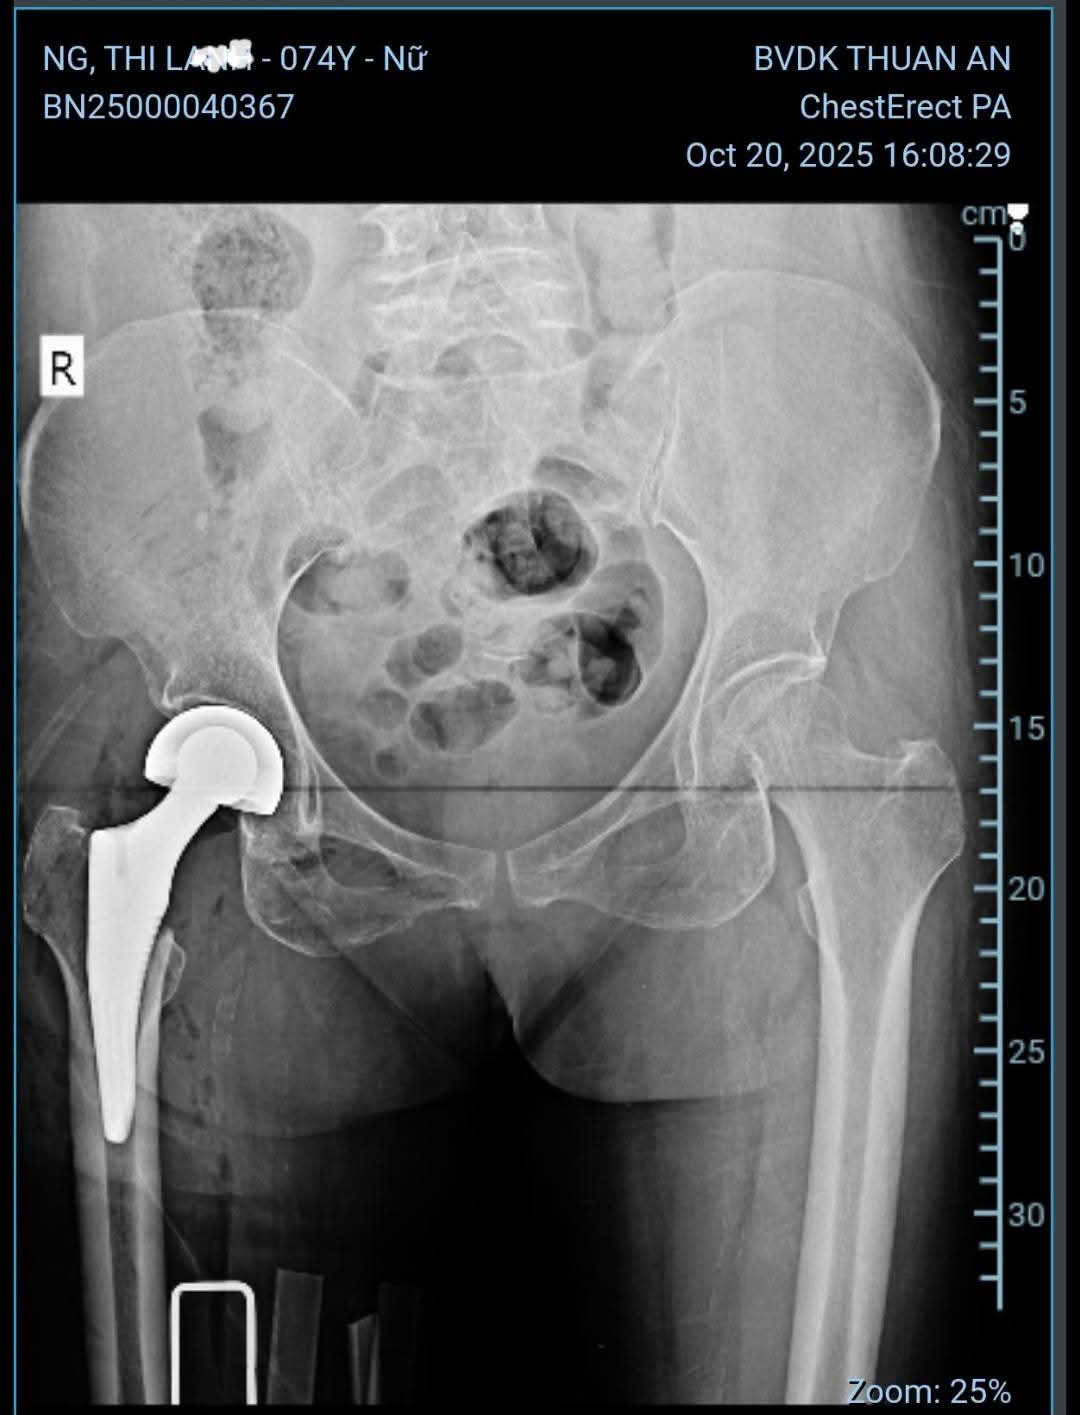

Gãy cổ xương đùi bên phải, Sau mổ thay khớp háng nhân tạo bán phần bên phải. Bệnh nhân bớt đau nhiều, có thể tự ngồi dậy sẽ tập đi lại trong vài ngày tới

Bệnh nhân nữ 74 tuổi gãy cổ xương đùi bên phải do té ngã và Sau mổ thay khớp háng nhân tạo bán phần bên phải. Bệnh nhân bớt đau nhiều, có thể tự ngồi dậy sẽ tập đi lại trong vài ngày tới